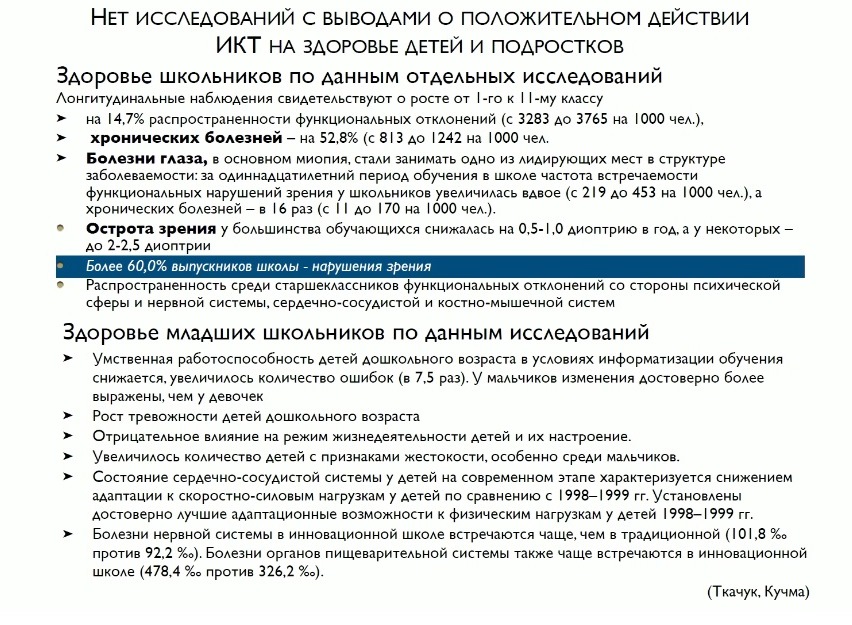

Что касается роста новообразований у детей – могу сказать, что эпидемии нет, но рост числа опухолей совершенно четко наблюдается с момента начала пользования населения гаджетами. Это около 500 случаев в год – не очень много с точки зрения общей статистики, но корреляция видна четко. И нет ни одного серьезного исследования, которое бы говорило, что действия комплекса возникающих факторов – от ЭМИ до оптики, зрительной и двигательной нагрузки – что все это безопасно и не вредно для детей.